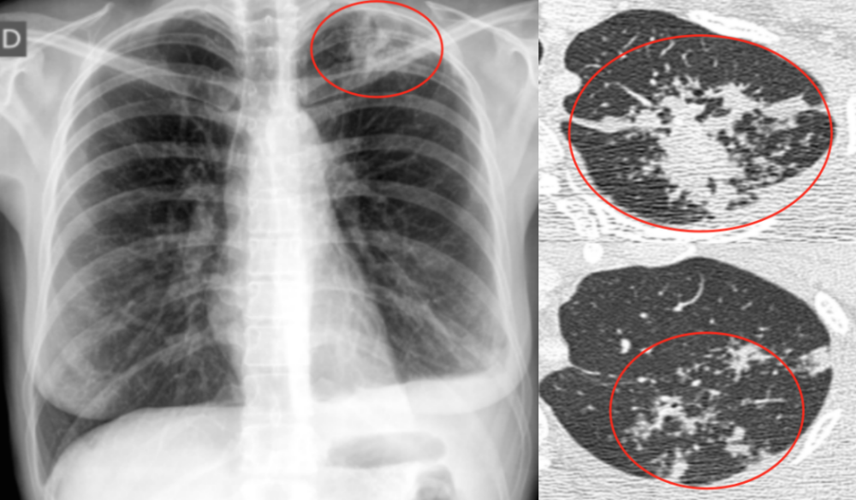

各型肺结核的典型影像表现

肺结核ct影像

肺结核ct影像表现特点

结核ct影像表现图片